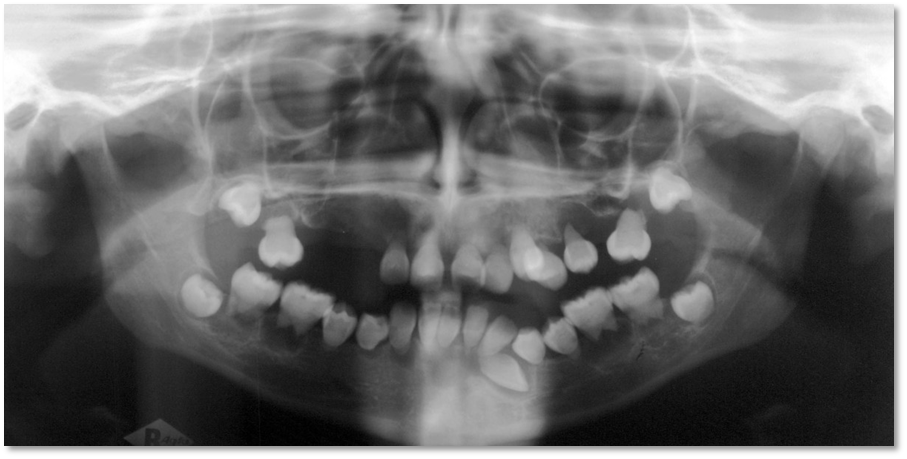

Enamel Hypoplasia (Figure 2)

Enamel Hypoplasia is defined as an incomplete or defective formation of the organic enamel matrix of teeth.12 Different types of enamel hypoplasia have been identified such as pit type, plane type and linear enamel type [13].

Enamel hypoplasia or hypo mineralization may be caused by hereditary factors and environmental factors that include systemic factors such as nutritional factors, exanthematous diseases like measles and chicken pox, congenital syphilis, hypocalcemia, birth injury or premature birth, fluoride ingestion or idiopathic causes, and local factors such as infection or trauma from a deciduous tooth.

Figure 2: Enamel Hypoplasia

PindborgJJ, (1970)14 showed that 3 to 15% of young adults had enamel hypoplasia in the permanent teeth and Pedersen (1944) reported that 14% of 2- to 4-year-old children had mild enamel hypoplasia in the primary teeth.15

The spots may be localized or generalized and may involve only enamel or enamel and dentin.

Enamel hypoplasia due to trauma may vary from white to mild brownish discoloration of the enamel to severe pitting and irregularity of the crown of the tooth.16

Enamel hypoplasia presents with unfavourable aesthetics, increased dentin sensitivity, increased dental caries susceptibility, increased wear and malocclusion.12

It can occur in any permanent tooth, the most commonly involved sites of hypoplasia are the permanent first molars and incisors with specific areas of defect and well demarcated areas of hypomineralization.

Environmental enamel hypoplasia/hypomineralization due to systemic factors are commonly manifested in the first permanent molars and incisors. It involves those teeth that form within the 1st year of birth. So, most frequently incisors and first permanent molars are affected. Hence, this condition is termed as “molar incisor hypomineralization.”

Environmental enamel hypoplasia / hypomineralization due to local factors is also called as “turners hypoplasia/ hypomineralization” seen most commonly in permanent maxillary incisors or upper lower premolar [15]